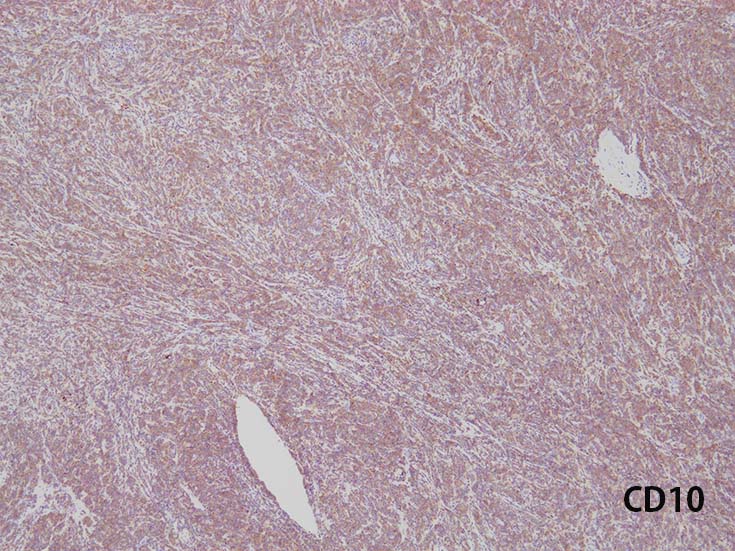

- T-ALL はしばしば, CD4とCD8の double positive となる. またCD10が陽性になる

- CD4,CD8 double positiveはT-prolymphocytic leukaemiaでも認められる. CD10もPTCL(第一にはAITL)に陽性となることに注意.